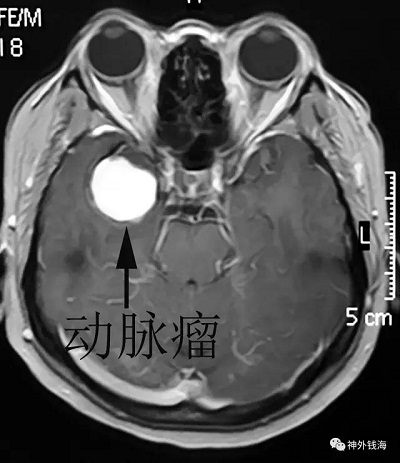

患者女性,37岁。主因“头痛20天”在当地医院行头部磁共振检查,考虑颅内巨大血栓性动脉瘤转入我院。

上图为当地医院的磁共振检查,可见右侧颞部巨大动脉瘤。